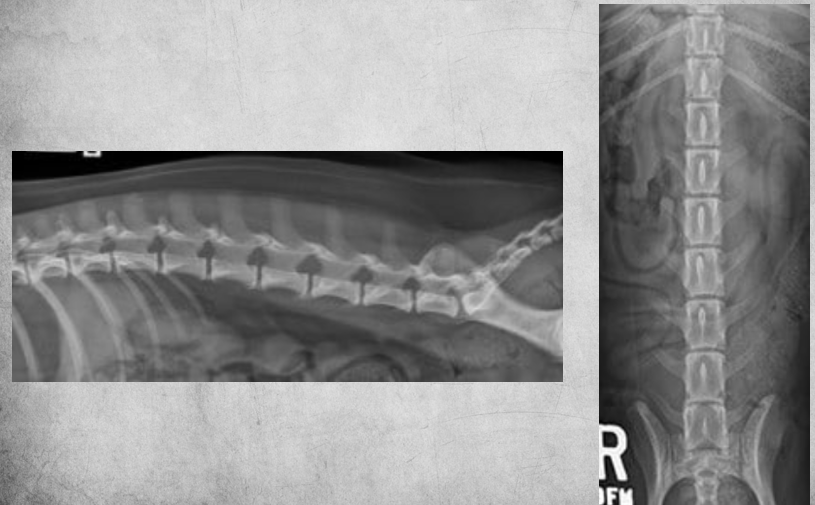

identify pathology

hyperparathyroidism in a 8 month kitten fed with sausages - image shows bendy back and sternum. - spinous processes not even visible anymore. pelvis poorly visible. - no secondary fractures yet. Can be treated with dietary change (Ca:P!!) but the bones will never return to normal.